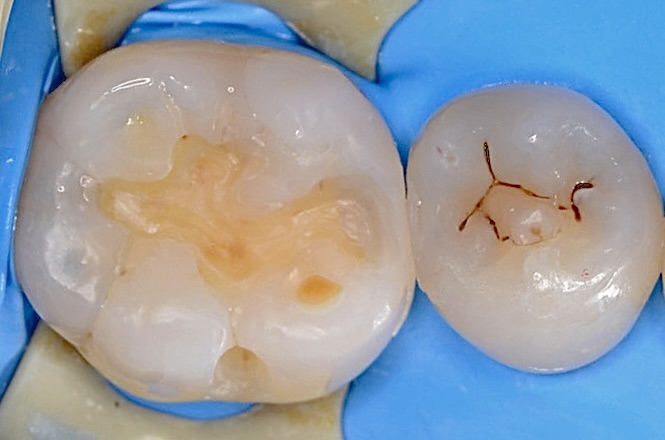

レジン充填

フロワブルレジンの表面張力を利用して、滑らかで継ぎ目のない修復ができました。 -

咬合面観

-

隣接面を少しづつレジン充填します。 -

隣接面部を適切な強さでレジン充填しました。 -